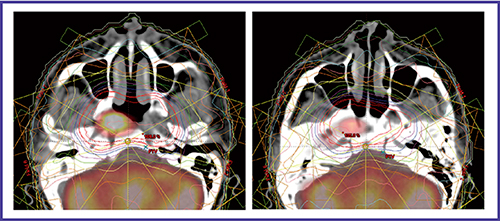

強度変調放射線治療(intensity modulated radiation therapy:IMRT)は,このような放射線療法の限界を解決できる先進的な照射技術である1)。放射線ビームの強度が均一な従来の放射線治療とは異なり,IMRTでは不均一な線量強度を有する多方向からのビームで照射する。IMRTでは,標的体積およびリスク臓器の形状に合わせた線量を照射できるため,正常組織への影響を最小限に保ちつつ,腫瘍に対しては高線量照射が可能となる(図1)。

図1 頭頸部癌に対するIMRTの線量分布図